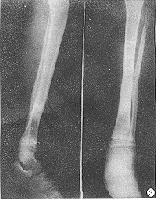

胫骨位置表浅,局部症状明显,加上X线检查,诊断并不困难。但应注意骨折的合并症,仔细检查软组织损伤程度,及时发现症状,及时处理。

x线检查在胫腓骨骨折中用于诊断、估计骨折愈合的程度、发现骨折的并发症及、做必要的鉴别诊断。

在临床上,一旦怀疑有胫腓骨骨折,就要拍摄小腿正侧位的X线片,照片质量要求较高,除了能发现明显骨折外,对怀疑的线状裂纹也要确定,因为线状骨折也影响愈后和治疗,如行内固定,其稳定性要把线状骨折的因素考虑在内。

在骨的x线描述上,首先确定骨折的部位,在上l/3、中l/3或下1/3。再确定骨折类型是横断、斜行或螺旋型骨折,骨折有无粉碎,以及是否多段。侧方移位严重则愈合很难。×线片上不易确定上下骨折段的旋转移位,要从临床上来判断和纠正。

X线正位片应包括胫腓骨全长,以免漏诊。X线可见骨折线、碎骨片、断端移位等。